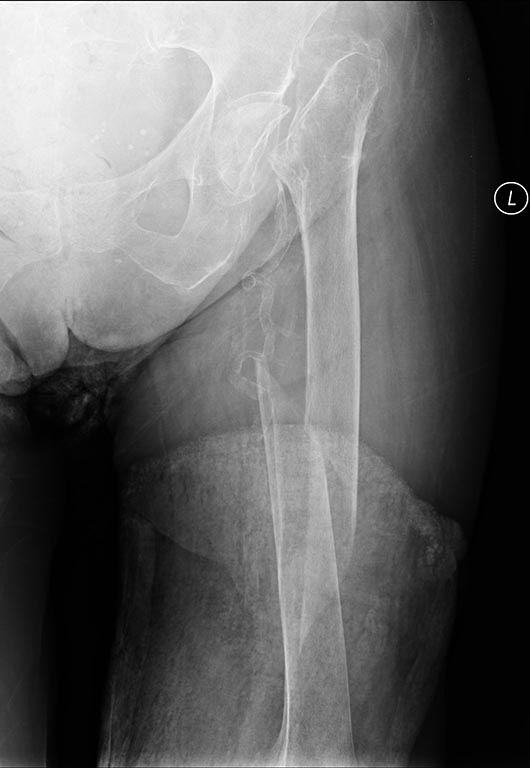

Женщина 87 лет. В 2006 году перелом шейки бедра слева, от операции тогда воздержалась. Последние 7 лет не ходит, со слов родственников передвижения иногда на коляске. 3 недели назал упала с кровати и сломала диафиз того же бедра. Объективно: истощена, вес 45 кг, пролежень (пока поверхностный)ягодичной области. Продуктивному контакту трудно доступна в т.ч. из-за глухоты. вторая нога с выраженным вальгусом в коленном суставе, движения сохранены.

Рентгенограмма бедра прилагается, выраженный остеопороз, кососпиральный перелом с/3.